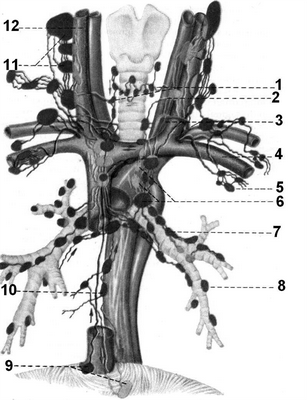

Рис. 2.29. Расположение лимфатических узлов шеи и средостения (схема).

1 - nodi trachealis; 2 - a. carotis communis; 3 - ductus thoracicus; 4 - v. subclavia; 5 - nodi lymphatici axillares; 6 - nodi tracheobronchiale; 7 - nodi bronchopulmonales; 8 - nodi pulmonales; 9 - nodi phrenici; 10 - nodi mediastinalis; 11 - nodi cervicales profundi; 12 - v. jugularis interna.